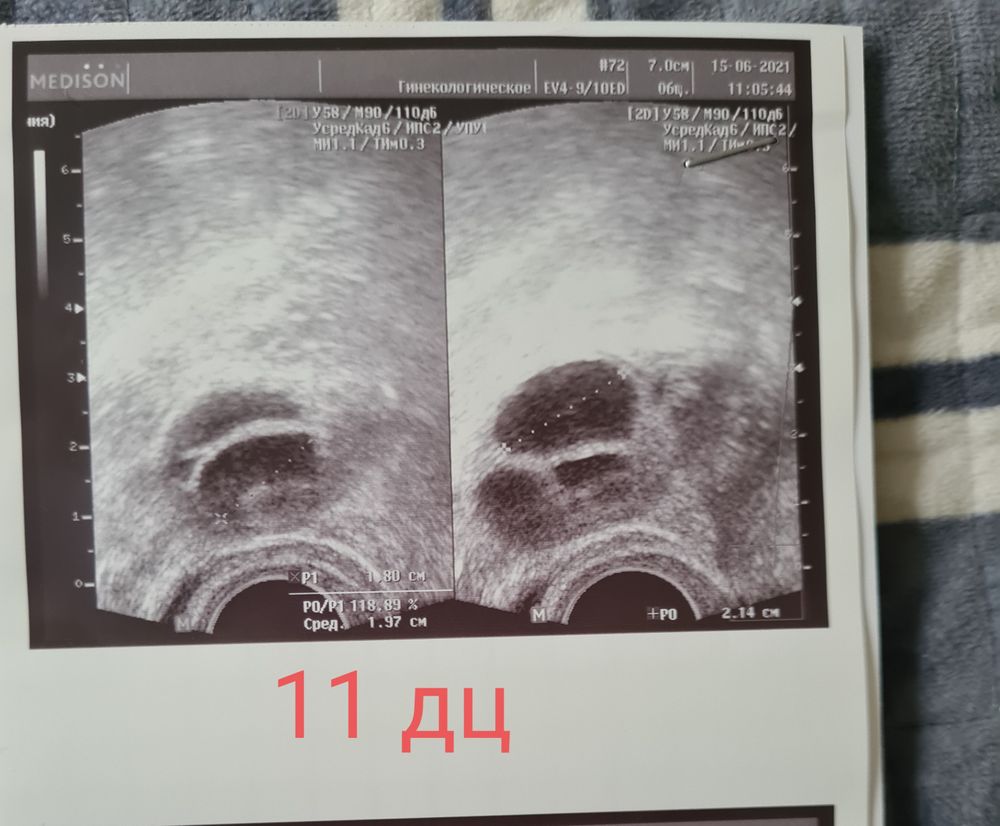

Куда пропали ДФ в ЛЯ?

Судя по желтым телам, у вас должна быть тройня,если беременность получится. Что ж это за врач такой что столько ЯК повыходило сразу

Юлия Л, она мне назначила Летрозол 5 дней по 2 таб и ростом 5 дней ещё Тамоксифен по 2 таб. Но Тамоксифен я пила только 2 дня. У меня и в прошлом цикле было 3 жт, но беременность не случилась...( Надеюсь в этом месяце хотя бы 1 из них оплодотворится благополучно

Меньше читайте😄 это первый совет. Второе-женский организм настолько не предсказуем, что может быть, что угодно. У меня стимуляция уже пятый цикл. Всегда перед овуляцией одно количество дф, а после овуляции жт больше обычно. Дело в том, что хгч способствует росту тех фолликулов, которые тоже стремились стать доминантными. А вот отката по росту не должно быть, если фолики уже больше 15. Может узист что-то не досмотрела? Хотя, опять же. Это организм. Может быть что угодно. С па вы угадали. Можно ещё сегодня закрепить, так как яйцеклетка живет до 48 часов, но обычно сутки.

После овуляции ЖТ формируется не сразу, некоторым нужен день-два на то, чтобы его увидеть на узи. Если повторите узи через пару дней думаю найдутся пропавшие. Про поводу ПА: спермотрзоиды готовы ждать яйцеклетку до 7 дней 🤗

Эндометрий на 10 дц Сходила на узи 8 дц